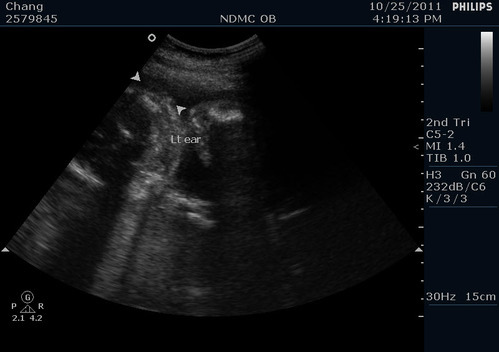

右邊的耳朵

左邊的耳朵

兩個耳朵大小高度都正常~沒有小耳症